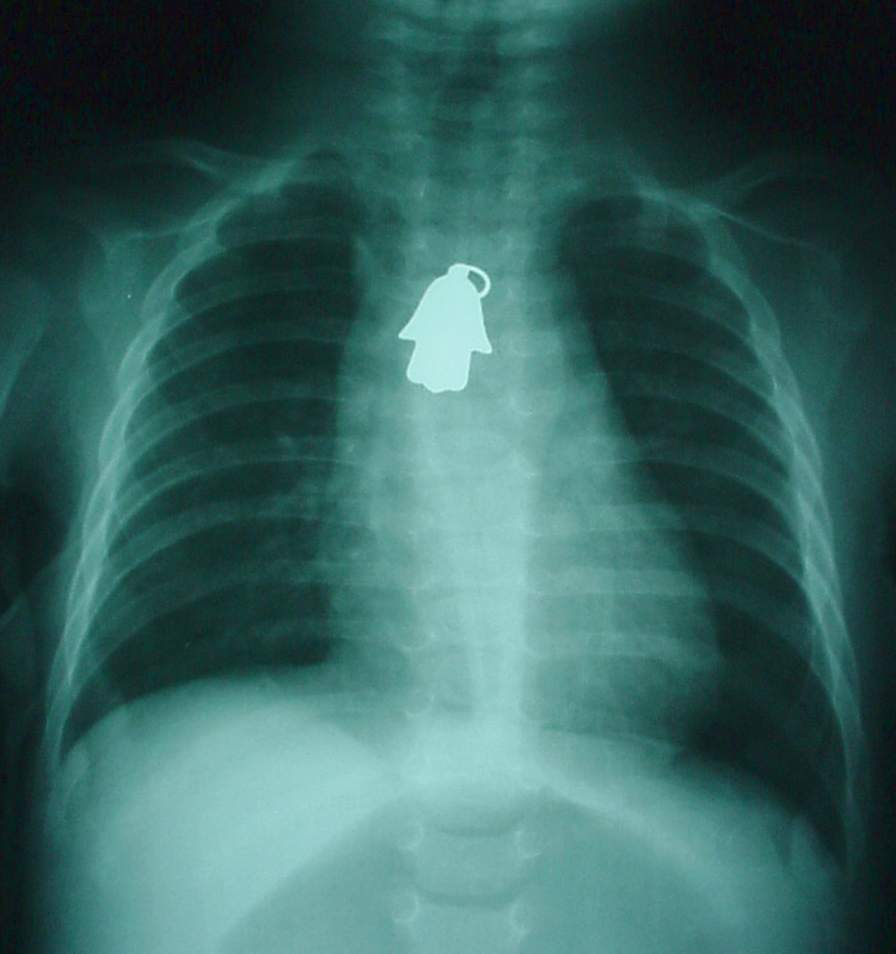

Pharynx and Esophagus Clinical Photos for Static Stations